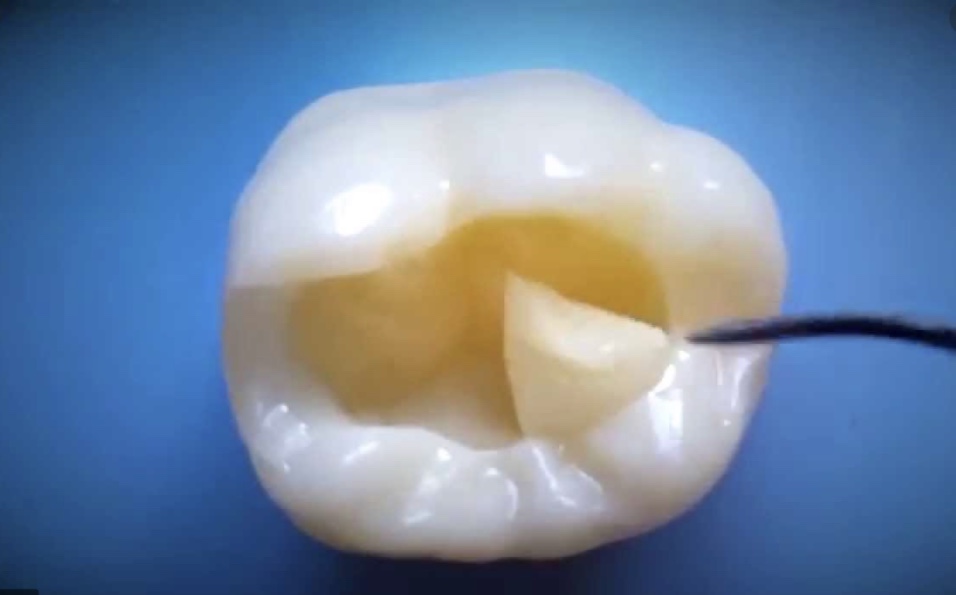

Techniques les plus modernes, les moins invasives et les plus durables pour restaurer lintégrité des dents

Soins conservateurs

Usure avancée

Traitements des cas dusure importante des dents liée au bruxisme, aux attaques acides ou aux brossages trop vigoureux.